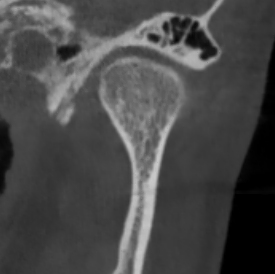

Перед началом лечения я провожу часовую первичную консультацию. Для этой встречи вам необходимо сделать «МРТ ВНЧС» и «КЛКТ двух челюстей с захватом ВНЧС в привычном прикусе».

Во время консультации мы смотрим и анализируем ваши исследования. Я подробно объясняю строение ВНЧС, показываю все причинные факторы вашей проблемы, отвечаю на все вопросы «Почему?»